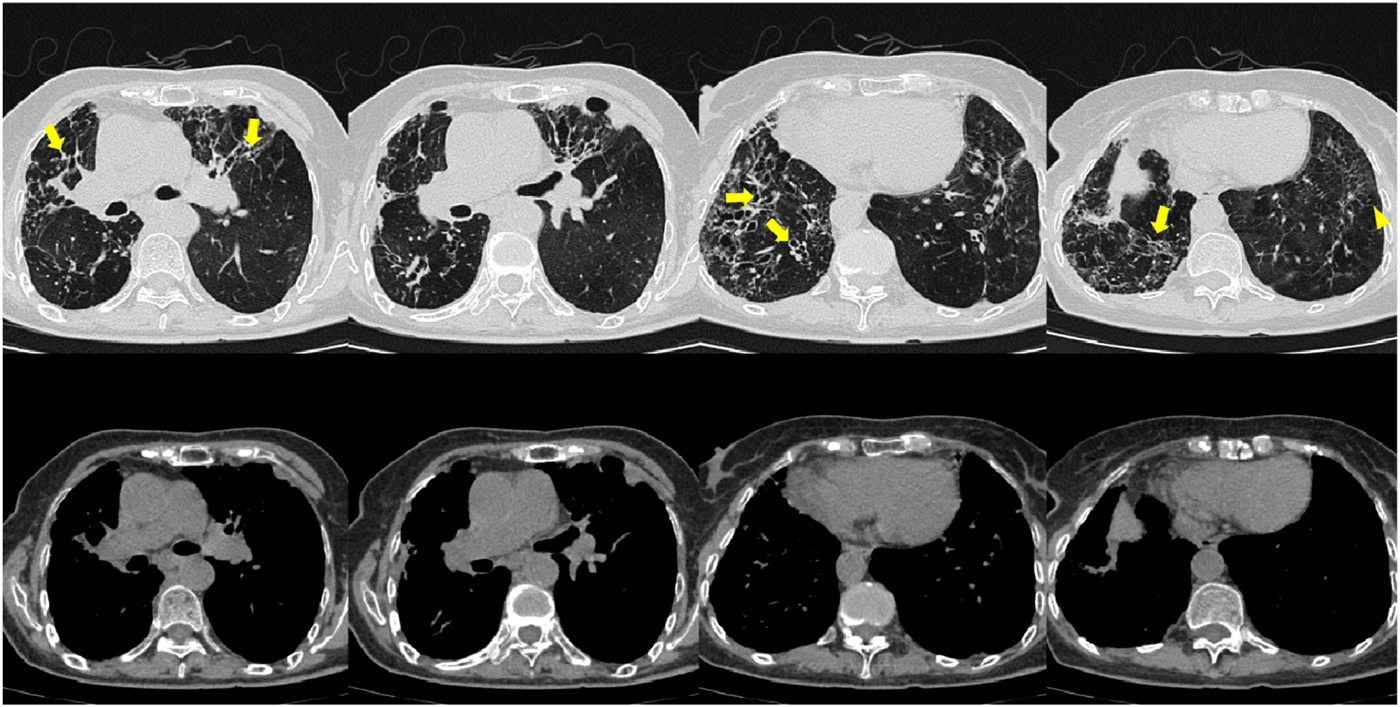

From June to September 2024, the patient followed up at the outpatient clinic. Chest CT showed that the lesions in both lungs were partially absorbed (Figures 5, 6), inflammatory markers returned to normal (Table 1), FeNO and peripheral blood eosinophils significantly decreased (Table 1, 3). By asthma symptom assessment, the patient’s cough severity score on the Cough Evaluation Test (CET) was 7, the Asthma Control Questionnaire (ACT) score was 25, and the Asthma Control Questionnaire-5 (ACQ-5) score was 0.8, indicating a significant improvement in pulmonary ventilation function (Table 2).

FIGURE 6

Patient’s chest CT imaging on Sep 12, 2024. The chest computed tomography showed stable disease of bronchiectasis (bold arrows) and chronic pleuropulmonary fibrosis (triangles), indicating the disease was consistently under control.